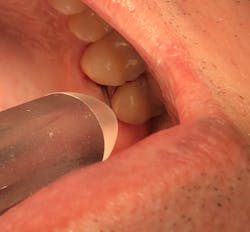

Depending on your state, some common procedures dental hygienists can perform with lasers are laser bacterial reduction (figure 1) and laser-assisted periodontal therapy (figure 2).1-3

Laser-assisted periodontal therapy (LAPT) can be used for active periodontal therapy (SRP with laser decontamination) and in conjunction with traditional deep scaling appointments. LAPT is the practice of administering laser energy within the periodontal pocket for profound decontamination. LAPT also results in increased tissue interaction by removing the inflammatory factors, significantly reducing bacteria within the pocket, and consequently promoting growth factors for healing with the goal of tissue rehabilitation. This procedure allows the tissue to heal and new attachments to form, making the pocket easier to maintain. Moreover, laser therapy in general is antimicrobial and decreases virulent red-complex bacteria, which can invade soft tissue and enter blood vessels, affecting overall health.1,5,6